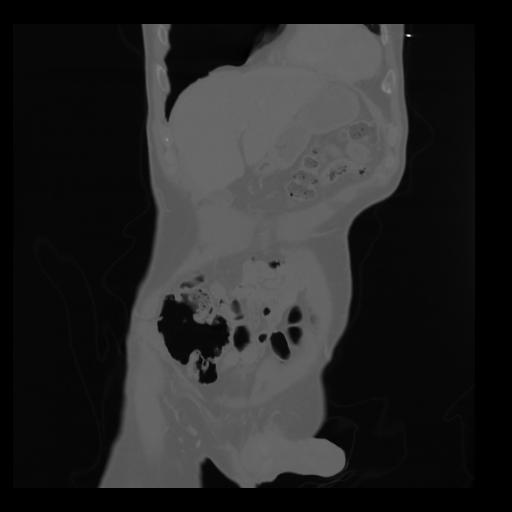

35 CUERPO,CE,Coronal,3.000,CUERPO,Coronal,